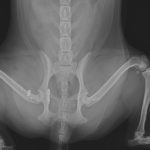

股関節脱臼に対するBUSTOR #67

輪禍外傷による股関節脱臼の患者さんに対してBullet–Shaped Toggle Rod (BUSTOR)で整復を行いました。本症例は恥骨の骨折も併発していたため、CTで寛骨臼の評価も実施しました。低侵襲かつ短時間で整復が可能です。しばらくは安静が必要です。